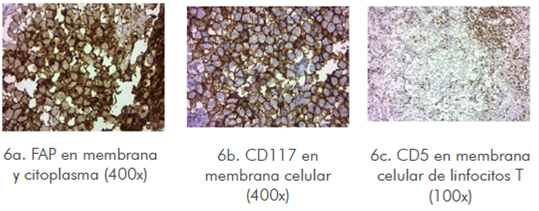

Imagen 6 La tinción de inmunohistoquímica por Fosfatasa alcalina placentaria (FAP), CD117 y CD5 con ácido peryódico de Schiff identificó labilidad para diastasa. Inmunohistoquímica positiva para FAP (Imagen 6a) en un patrón de membrana y citoplasma, así como CD117 (c-kit) en membrana (Imagen 6b), estudio con CD20 (linfocitos B) y CD5 (linfocitos T) focalmente positivos en los linfocitos que característicamente forman parte del tumor.

En este escenario la biopsia de tejido subependimario con arquitectura histopatológica para germinoma, se complementó con marcadores tumorales negativos e inmunohistoquímica positiva para fosfatasa alcalina placentaria (FAP), pruebas consideradas estándar de oro para germinoma1,4,5,7.